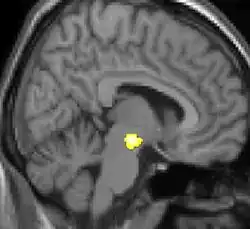

VBM mostrando diferenças estruturais entre cérebros

As reais causas da cefaleia em salvas (CES) ainda são desconhecidas, mas, de acordo com alguns estudos, os padrões das crises, as influências pelo horário do dia e as estações sugerem que o relógio biológico do corpo está envolvido. Nos seres humanos, o relógio biológico está situado no hipotálamo. Durante um ataque, o hipotálamo libera substâncias químicas que podem estimular as células nervosas no cérebro, causando dor e outros sintomas. A hiperatividade nervosa também pode causar um alargamento (vasodilatação) das artérias no lado afetado do cérebro. Uma teoria é que as dores são causadas por um alargamento dos vasos sanguíneos, que pressionam sobre os tecidos nervosos próximos, causando dor.[5] Exames de ressonância magnética sugerem dilatação da artéria oftálmica durante uma crise de cefaleia, enquanto a tomografia por emissão de pósitrons (PET) revela atividade dentro do seio cavernoso. Em alguns casos, existem fatores genéticos também, pois é mais comum entre familiares.[6]